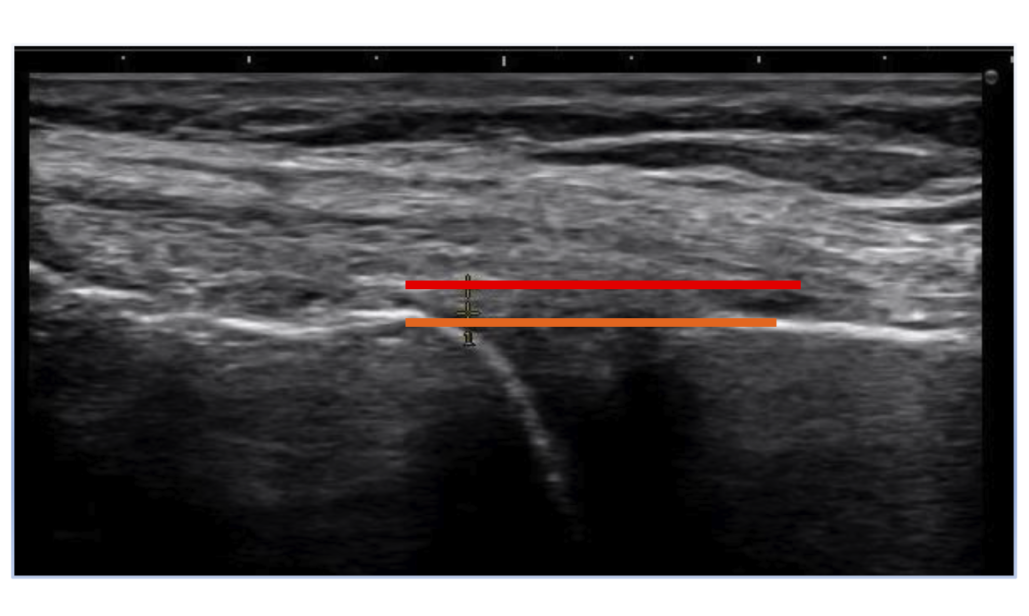

大腿骨と脛骨の内側縁を結ぶライン、 ——— 赤線は内側半月の偏位 ———